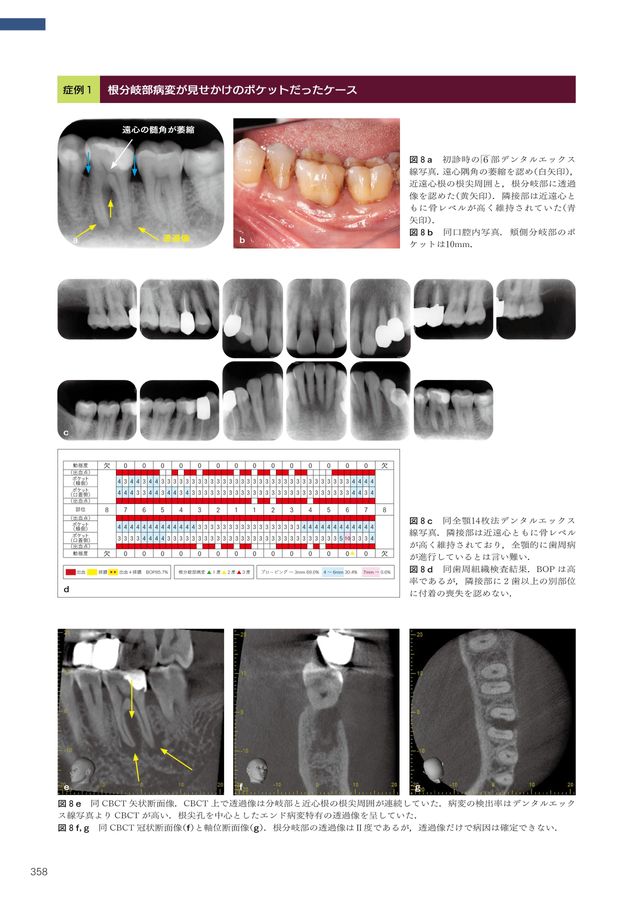

裁断済み 5-D コンセンサス 歯の保存にこだわる。4/10(木) 5-Dコンセンサス 歯の保存にこだわるが発売されました! | 5。4/10(木) 5-Dコンセンサス 歯の保存にこだわるが発売されました! | 5。5-Dコンセンサス 歯の保存にこだわるこれまでの軌跡と次世代へのメッセージ石川知弘・北島一・福西一浩・船登彰芳・南昌宏【監著】藍浩之・石川亮・片山明彦・菊地康司・丹野努【著】2025年04月10日 A4判 480頁29,700円(税込)クインテッセンス出版裁断済みです。5-Dコンセンサス 歯の保存にこだわる。